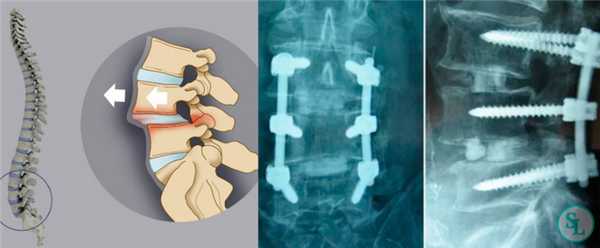

Транспедикулярная фиксация или ТПФ - операция, при которой позвонки фиксируются и стабилизируются при помощи специальных имплантов (транспедикулярных винтов). В каждом позвонке есть точка ввода винта, которую установил в 1985 году Рой Камилл — это точка пересечения поперечного отростка позвонка с верхнем суставным отростком. С помощью специальных инструментов в эту точку, вкручиваются винты определяя анатомически правильное расположение позвоночника, тем самым излечивая заболевание. Первые попытки установки имплантов были в 60-70 гг. прошлого века и с тех пор является «золотым стандартом» в лечения переломов и различных заболеваний позвоночника.

Межтеловой кейдж для фиксации позвонков

Чтобы операция дала наилучший результат, часто используется межтеловой кейдж, который должен отвечать таким требованиям:

- обеспечивать стабильность тел позвонков;

- гарантировать сохранение нормальной высоты межпозвоночных дисков, что позволяет избежать компрессии нервов;

- быть изготовленным со специальным пространством через которое, можно вводить костный цемент, искусственную костнозамещающую крошку или препаратов увеличивающих рост костной ткани ;

- Корригировать и фиксировать боковой (сагиттальный) и передний (фронтальный) баланс позвоночника;

- Удерживать нагрузку которая ложиться на ось позвоночника.

Безусловно, предельно качественное выполнение ТПФ обеспечивается при применении устройств 3-го поколения. Современные имплантируемые кейджи позволяют надежно зафиксировать патологически измененный сегмент позвоночника и устранить болевой синдром, обусловленный его остаточной подвижностью.

Размер закрепляющих винтов для каждого больного подбирается индивидуально. Различают моноаксиальные и полиаксиальные винты, также разработаны варианты с боковой фиксацией стержня. Они вводятся по конвергентной монокортикальной методике, подразумевающей перфорацию позвонка только в точке входа винта.

Точка установки винта в корень дуги подбирается на основании расположения двух анатомических ориентиров - поперечного и суставного отростков позвонка. Непосредственно позвонок перфорируют с помощью специального зонда.